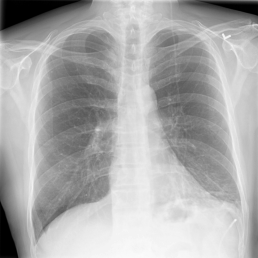

The wide variety of in-distribution and out-of-distribution data in medical imaging makes universal anomaly detection a challenging task. Recently a number of self-supervised methods have been developed that train end-to-end models on healthy data augmented with synthetic anomalies. However, it is difficult to compare these methods as it is not clear whether gains in performance are from the task itself or the training pipeline around it. It is also difficult to assess whether a task generalises well for universal anomaly detection, as they are often only tested on a limited range of anomalies. To assist with this we have developed nnOOD, a framework that adapts nnU-Net to allow for comparison of self-supervised anomaly localisation methods. By isolating the synthetic, self-supervised task from the rest of the training process we perform a more faithful comparison of the tasks, whilst also making the workflow for evaluating over a given dataset quick and easy. Using this we have implemented the current state-of-the-art tasks and evaluated them on a challenging X-ray dataset.